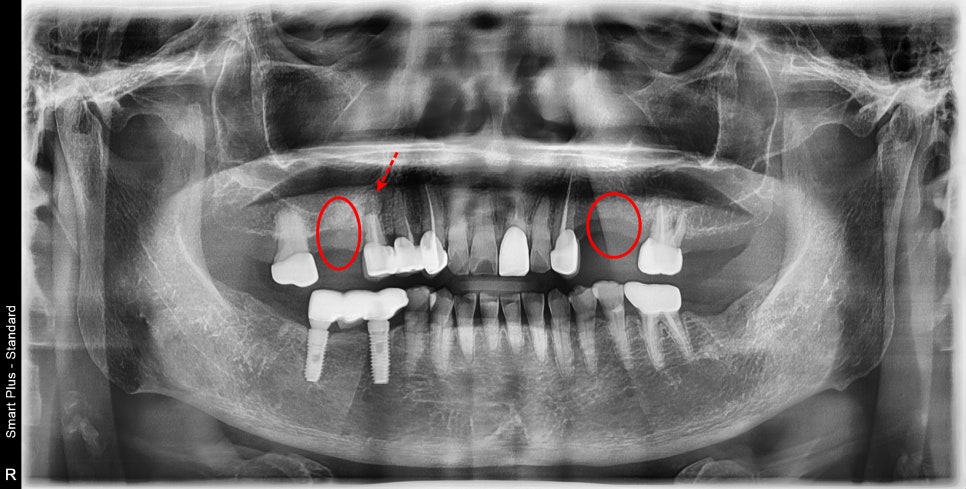

치아가 3개가 상실된 상태이셨는데

과거에 임플란트 대신 이 부분에 부분 틀니를 걸어서 사용하고 계셨습니다.

부분틀니를 쓰기 위해서는 주변 치아들에 틀니가 거는 힘이 가해지기 때문에

오래 유지했을 경우 주변 치아에 문제가 생기는 경우가 있습니다.

염증이 어느 치아에서 시작되는지 검사를 통해 알아냈습니다.

고리를 거는 힘을 받는 앞 치아 뿌리 쪽에 염증이 생기고

그 염증이 잇몸 바깥으로 염증 주머니를 만들어서 불편감을 일으키고 있었습니다.

틀니의 거는 힘에 의해 앞 치아가 반복적으로

무리한 힘을 견뎌 녀는 과정에서 뿌리의 흡수와 염증반응이 생긴 것입니다.